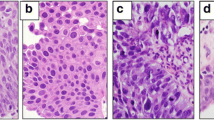

Grading by pathologists

Five pathologists graded each tumor image. To increase the resolution, the grading was on a scale of grade 1, the lowest grade, to grade 5, the highest grade (Fig. 1). In addition, two expert genitourinary pathologists (I.F. and G.G.) graded the tumors in a similar manner. Both expert pathologists are dedicated genitourinary pathologists with over 5 years of experience in genitourinary pathology. The grading by pathologists was performed by assessing all the conventional histologic features that determine the tumor grade, and these include nuclear pleomorphism, hyperchromasia, loss of polarity and crowding. All images were anonymous and the pathologists had no access to personal information of participants.